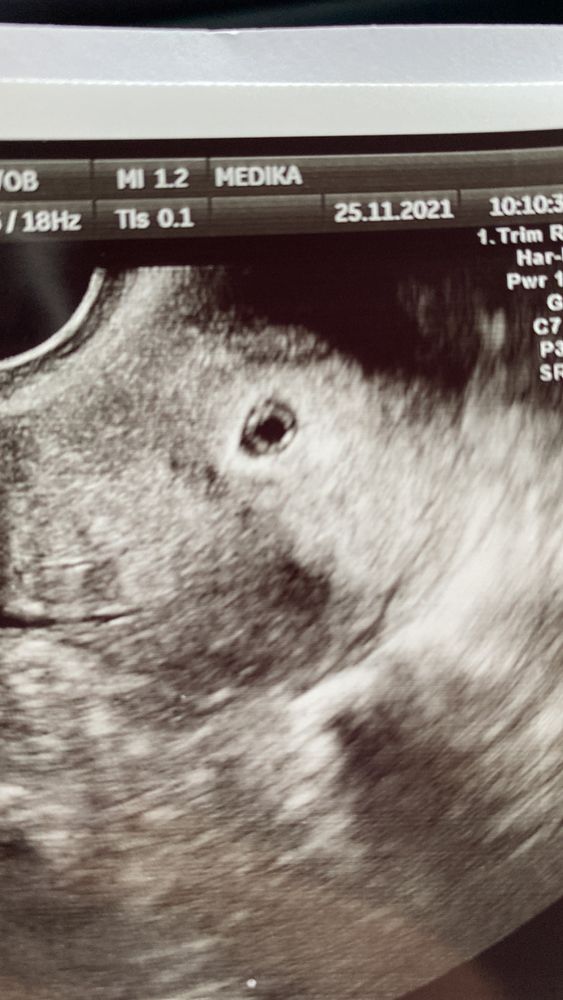

вот так выглядит))) Само яйцо маленькое